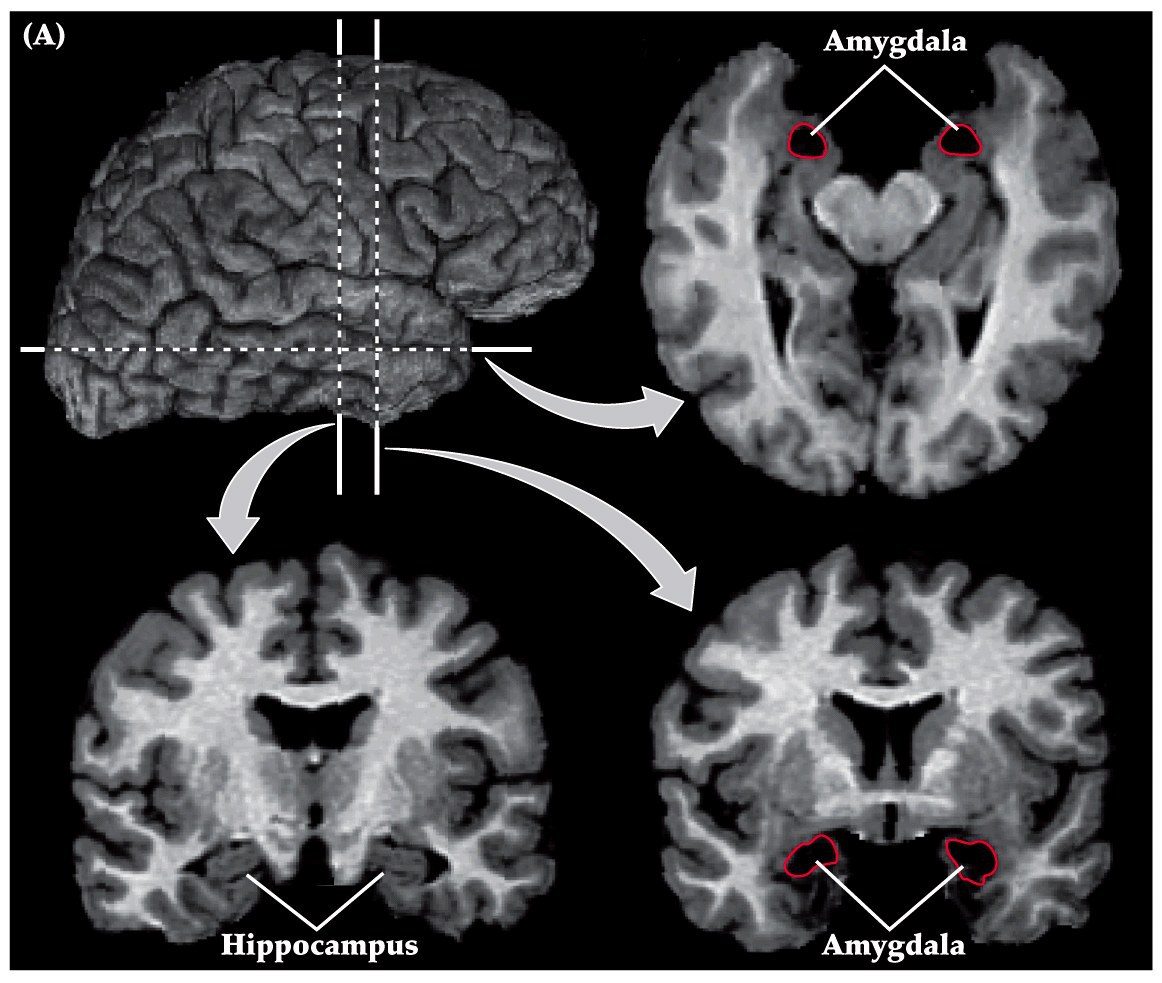

Amygdala

amgydala is in the anteior-medial part of the temporal lobe. Rostral to hippocampus

- John Downer (London in 1950’s) removed the temporal lobes of monkeys and witnessed weird emotional behaviors

- Unable to recognize objects, although not blind (why?)

- Bizarre oral behaviors

- Hyperactivity and hypersexuality, making physical contact with virtually anything

- No longer showed fear. Neither to humans or to snakes

- Eventually the fear behaviors was narrowed down to a region called the amygdala through selective lesion studies

Patients with amygdala damage exhibit diminished emotional fear recognition and expression

Patient S.M. can’t recognize the emotion of fear in photographs. She also exhibits little fear herself (e.g. to dangerous animals, scary houses, films, etc)

patient SM has rare autosomal recessive condition called Urbach-Wiethe disease. Disorder of bilateral calcification an atrophy of anterior-medial temporal lobes. Both amygdalas are extensively damaged. Little to no injury of the hippocampus.

She has no motor or sensory or intelligence or memory or language impairment. However she can’t recognize the emotion of fear in photographs. Furthermore, she exhibits little fear herself (to dangerous animals, scary houses, films, etc).